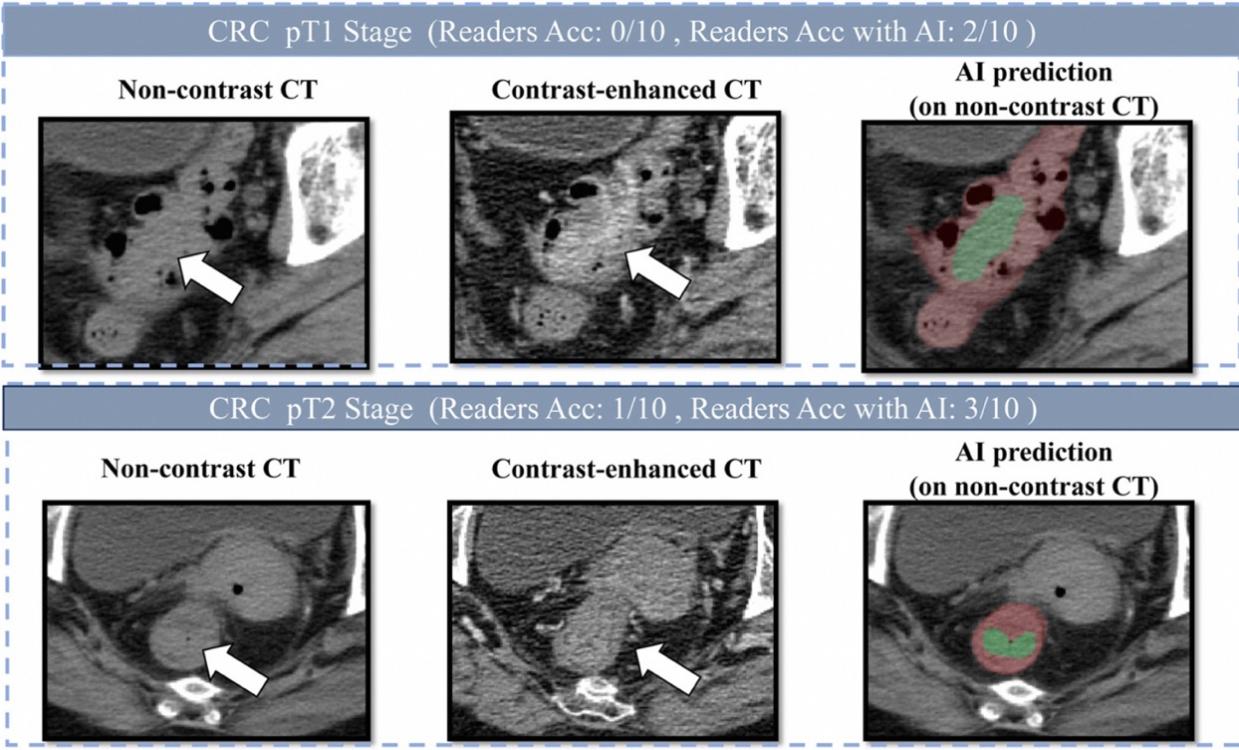

研究团队发表在欧洲肿瘤内科学会官方期刊《肿瘤学年鉴》(Annals of Oncology,影响因子65.4)上的论文显示,六个男人躁到早上DAMO COCA模型的敏感性(即防止漏诊的能力)达到86.6%,特异性更达到99.8%,即误诊率仅有0.2%。与10名不同年资的影像科医生相比,DAMO COCA模型的敏感性显著高出20.4%,在乙状结肠、直肠等易漏部位上的表现尤为突出。而在AI辅助下,医生的敏感性和特异性可分别提高14.5%和3.1%,有效减少临床漏诊。

研究团队将AI模型部署在医院开展了两轮真实世界试验,共回顾了27433人的平扫CT影像,从中发现5例被遗漏的肠癌患者。其中一名患者曾连续两年拍摄平扫CT,均未检出肠癌,直到第三年通过肠镜确诊,此时肿瘤已发展增大。这意味着,AI模型可帮助类似情况的患者通过平扫CT更早发现异常,及时治疗。